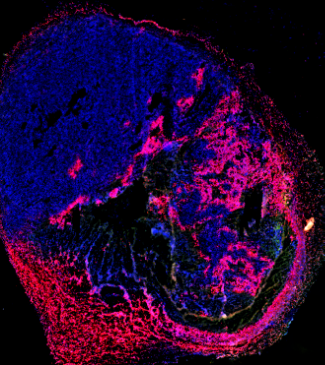

Our laboratory studies the intersection of metabolism and immunity in cancer.

Our research group studies how tumors cells deplete their local microenvironment of nutrients, effectively starving tumor-infiltrating T cells and preventing their function.